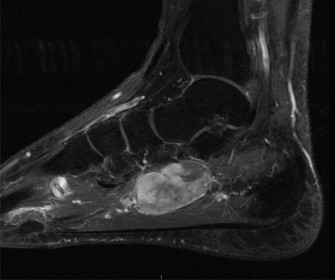

Figure 1: Representative Sagittal T2-weighted MRI image demonstrating a severely displaced talar neck fracture (Hawkins type III/IV). Note the significant angulation and posterior displacement of the talar body relative to the ankle mortise, and extensive bone marrow edema. The fracture line extends into the posterior subtalar joint. Soft tissue swelling and potential ligamentous injury are also evident.

• Crucial MRI Sagittal Insights:

The MRI sagittal images proved indispensable for a complete understanding of the injury pattern, exceeding the capabilities of CT for soft tissue and cartilage assessment.

• Ligamentous Integrity: Sagittal views provided excellent visualization of the calcaneofibular ligament, posterior talofibular ligament, and particularly the deltoid ligament complex. In this case, significant edema and partial tearing of the deep deltoid ligament were noted, correlating with the medial clear space widening on X-ray. Sagittal images are also superior for assessing the interosseous talocalcaneal ligament, a critical stabilizer of the subtalar joint, which showed signs of disruption.

• Articular Cartilage Assessment: While CT shows bone, MRI sagittal views exquisitely demonstrate the integrity of the articular cartilage. We observed areas of chondral bruising and early subchondral edema on the talar dome, consistent with impaction. Furthermore, articular step-offs and incongruity in both the tibiotalar and subtalar joints were precisely quantified, guiding the need for meticulous anatomical reduction.

• Talar Head and Neck Morphology: The sagittal images provided a detailed profile of the fracture lines through the talar neck and body, allowing for precise measurement of anterior, posterior, and superior displacement and angulation. This was critical for understanding the extent of shortening and the specific vector required for reduction. They also helped identify small, non-displaced fracture lines or occult fractures that might be missed on CT, particularly in areas of complex anatomy.

• Subtalar Joint Involvement: The sagittal plane is paramount for evaluating the posterior facet of the subtalar joint. In our patient, the fracture clearly extended into this joint, with significant displacement of the posterior talar facet, highlighting the necessity for accurate reduction of this weight-bearing surface to prevent post-traumatic arthrosis.

• Associated Soft Tissue Injuries: Beyond ligaments, MRI sagittal views allowed assessment of surrounding tendons (e.g., flexor hallucis longus, posterior tibialis, Achilles tendon), demonstrating tenosynovitis or contusion which could impact post-operative recovery. Assessment of the posterior neurovascular bundle can also be achieved.

• Vascularity Assessment (Indirect): While direct visualization of vessels requires angiography, MRI provides indirect signs related to vascular compromise. The extent of fracture displacement and soft tissue injury can correlate with the risk of AVN. Advanced sequences, though not routine for initial trauma, can sometimes show perfusion changes.